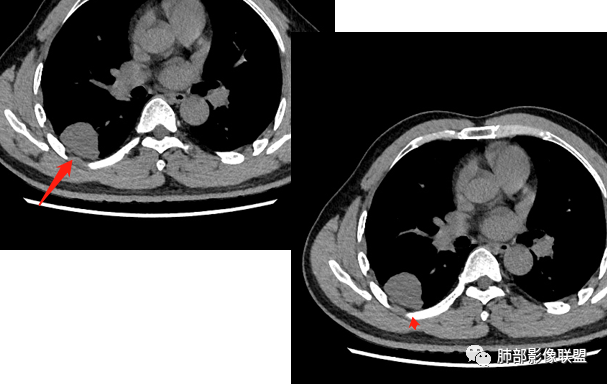

右肺下叶背段胸膜下见团块影,边缘清,其后基底段见一扁平状结节,各见‘’平直及桃尖"征,均轻度强化,右肺上叶背段及中叶外侧段分别少许纤维化灶及部分卫星病灶,一元考虑TB,与隐球菌鉴别!

右肺下叶胸膜下类圆形团块,边缘光滑无毛刺分叶,强化均匀无坏死,另血管旁小结节平直桃尖,上叶小斑片影,考虑结核或者真菌感染。

右肺下叶背段胸膜下见一边缘稍模糊、浅分叶结节灶,密度均匀,似乎轻度均匀强化(具体CT值看不出来),与胸膜锐角相贴,似有平直征和桃尖征。此病灶前内侧还有类似小结节,轻度强化,右肺上叶后段有斑片状稍高密度影:考虑良性病变,炎性结节可能。

晨读,右肺下叶背段胸膜下见肿块影,边缘清晰,未见与气管相连通,右下叶见结节影边缘清晰,两处病变密度均匀,同步不明显强化,中叶外侧段斑点状影,树芽征,考虑1良性病变,结核?隐球菌?2淋巴瘤待除外。

右肺下叶背段胸膜下宽基底团块状占位,浅分叶,边界清晰,胸膜下脂肪间隙清晰,背段支气管管壁似乎增厚,未见明显强化。外侧基底段血管束间结节,边界清晰,亦未见明显强化。中叶外侧段见少许树芽征象。纵隔未见明显肿大淋巴结。我先猜个结核。

男性,49岁,体检发现,右肺下叶背段胸膜下见肿块,边界清楚,边缘光滑,胸膜下脂肪间隙存在,有分叶,无毛刺,均匀强化,内无坏死,右肺下叶血管束间不规则实性结节,边界清楚,无明显强化,中叶少许斑片状高密度影,纵隔未见明显增大淋巴结,考虑良性病变。

右下肺占位并淋巴结肿大,边缘光滑,强化不明显,指状突起。考虑恶性肿瘤,不除外小细胞,鉴别诊断肺结核。

中年男性,体检发现病灶,右肺下叶背段胸膜下见团块影,边缘清晰,与气管关系不密切,右肺下叶见一小结节影,边缘清晰,两处病变密度均匀,增强病灶强化不明显,偏向良性病变,隐球菌?炎性假瘤?

右肺下叶肿块,边界清楚,边缘有晕,光滑,无毛刺,均匀强化,无坏死,中叶少许斑片状高密度影,粘液栓,考虑良性病变,隐球,鉴别结核。

中年男性,有吸烟史,右肺下叶靠近胸膜下类圆形肿块,边缘光滑,有膨隆,浅分叶,周围有磨玻璃影,附近有血管进入,与支气管关系不大,宽基底与胸膜相连,胸膜增厚不明显,密度均匀,轻度强化;右肺下叶近端有一不规则结节,有血管贴边征,右肺中叶外侧段斑片影。右肺下叶靠近胸膜下肿块考虑恶性神经内分泌肿瘤,大细胞肺癌可能性大。靠近肺门端结节考虑转移?右肺中叶炎症。鉴别隐球菌肺炎。

中年男性,无症状,右肺下叶背段团块影,边缘清晰,周围晕征,增强病灶强化不明显,考虑隐球菌。

右肺下叶二个大小结节,胸膜下结节浅分叶,指状突起,轻度强化,较小结节血管漂浮,考虑小细胞癌,类癌,鉴别隐球菌。

右肺多发结节,较大位于胸膜下,宽基底与胸膜相连,边缘光滑,分叶不明显,局部周围似有模糊GGO,支气管显示不佳,平扫密度均匀,增强后强化不明显,考虑良性,IMT,隐球菌,鉴别小细胞癌。

右肺下叶胸膜下肿块影,边界清晰,无明显分叶及毛刺,无晕征,未见明显卫星病灶,内无钙化,增强后均匀强化,未见明显坏死,近肺门侧小肿块,与血管无关,需要连续层面看与支气管的关系,无关就是淋巴道,考虑小细胞癌有可能,近肺门是淋巴转移途径?

体检发现右肺下叶胸膜下类圆形肿块,边界清晰,有膨胀感,胸膜下脂肪间隙清晰,密度均匀,增强轻度均匀强化。另右肺下叶血管束间可见一小结节影,与胸膜下大结节类似。考虑为良性病变。

中年男性,体检发现,有吸烟史。影像见右肺多个结节、肿块影,大者位于背段,靠近胸膜下类圆形肿块,密度较均匀,边缘光滑,有膨隆,浅分叶,周围有磨玻璃影,有血管进入,似与支气管关系不大,宽基底与胸膜相连、扶墙,轻度强化;纵隔内无明显肿大淋巴结。首先考虑炎性隐球菌可能,需鉴别:肿瘤病变转移。

中年男性,28年吸烟史,肺内多个病灶,较大病灶位于胸膜下,边缘较光整,宽基底,胸膜局限性增厚,支气管壁无明显增厚,与周围支气管关系不是很密切,不明显强化,常规考虑炎性病变,恶性小细胞癌属于崽大?

中年男性,20余年吸烟史,体检发现,右肺下叶胸膜下软组织肿块,边界清楚,边缘平直,有压迹,密度均匀,增强强化不明显,未见坏死区,考虑良性可能,炎性肉芽肿?。右肺下叶一小结节影,多个层面均有,考虑整体呈管状,走行与支气管相似,增强强化不明显,支气管来源可能,粘液栓?右肺中叶外周见斑点状、小结节状影,炎性病变?一元论,支气管来源病变,支气管囊肿?粘液栓?阻塞性炎症?长期吸烟史,鳞癌不除外。

右肺下叶胸膜下结节,膨隆为主,胸膜糊墙,类山丘正,邻近血管增粗,其内侧肺门方向另见一小结节,均轻度强化,强化程度类似,长期吸烟史,首先考虑小细胞癌,鉴别炎性结节。

中年男性,体检发现占位。右肺下叶背段胸膜下肿块,周围晕征,有小分叶,与支气管、肺内血管关系不清,形似山丘,重建可见肿块呈D字形凸向肺部。似跨斜裂,似有小凸起与肋下缘相连,增强似有轻微均匀强化。右肺下叶外基底段小结节,位于血管周围,部分边缘平直,轻微均匀强化。考虑二元:一、右下叶背段肿块为肺外病变,神经鞘瘤?SFT?鉴别小细胞癌、隐球菌病;二、右下叶外基底段结节考虑为良性结节、炎性肉芽肿?

大小两个结节,形态类似,强化一致,都是乏血供病变,也无明显坏死,不符合炎性肉芽肿强化特点了,大结节膨隆明显,有局部突出,有长期吸烟史,所以考虑神经内分泌肿瘤可能(小细胞>不典型类癌),另外不典型错构瘤需要鉴别。最终还是需要穿刺病理确定。

右肺下叶占位,胸膜下,与胸膜关系密切;

密度均匀;糊墙,边缘膨隆为主;

部分血管推移。

支气管如何?

秦化君: 似乎无关

张燕萍: 没看到堵塞哦落花时节: 没看到支气管进入南边:好,都在门口。

浅分叶

这个结节呢?

血管也是稍推移,在边缘,病灶密度均匀,边缘稍收缩;均匀强化;

这两个病灶的密度、强化、形态、边缘、与血管的关系类似;还是一元论吧。

2.右肺下叶背段胸膜下块影,边界清楚光整,上下极见磨玻璃晕,未见明显分叶毛刺和棘状突起,未见胸膜凹陷或胸壁侵入。密度均匀,轻度不均匀强化。未见支气管进入。

3.右肺中叶外侧段胸膜下散在小片影,磨玻璃密度为主,边界不清,支气管相关。符合炎性特征!

4.右肺下叶基底段支气管血管束旁小结节影,边界清楚,强化不明显。注意,这结节在“遥远的”基底段。